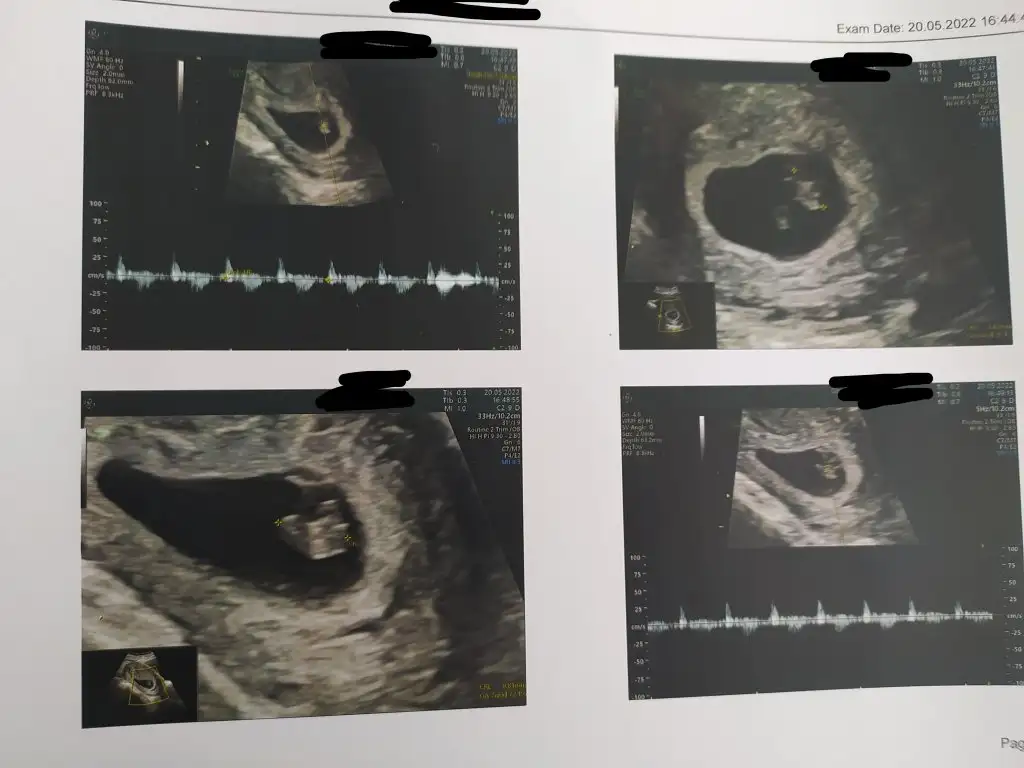

Çoook uzun bir süre araştırma okuma yaptıktan sonra sizlere bu başlığı açtım çevremde tüm gebelere de denedim. Bunun sırrını çözen İnstagramda (isim vermeyim) işi ticarete dökmüş bile.Nub, Ramzi,Çin Rus Japon Takvimleri, Yüzük Yöntemi bir çok şey size sayabilirim.

5 ve 14. haftaya kadar olan ultrason fotolarınızı paylaşın. Vajinadan mı yoksa karından mı çekildiğini ve kaç haftalık olduğunu da mutlaka belirtin.

Benim kızmış canımkuzucum erkek bebiş gibi görünüyor hakkında hayırlısı :) geri dönüş yapmayı unutma

görüntüyü biraz uzaktan çeker misiniz10+1 bana da yorum yapabilir misin

paşa gibi10+1 bana da yorum yapabilir misin